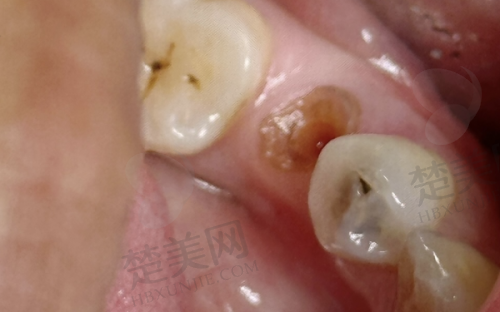

手术复杂程度对价格的影响:骨量充足,如果你的骨量充足,可直接种植,费用就会比较低。需要骨增量/上颌窦提升,要是需要骨增量或者进行上颌窦提升手术,就需增加骨粉或骨膜材料,费用可能会提高3000 - 8000元。

其他可能产生的费用:术前检查,包括CT扫描、口腔全景片等,费用约300 - 800元。拔牙/牙周治疗,若需要处理残根或炎症,费用要另计。个性化美学设计,前牙种植对牙龈形态、牙齿比例要求较高,可能会涉及数字化设计费用。